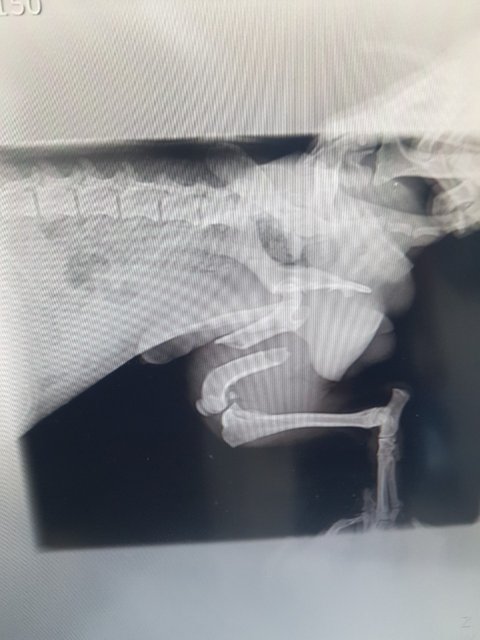

뒷다리골절 덜렁거리는 다리로 꼬리를 흔들며 다가와 눈을 맞추던 아이..

눈속에 많은것을 담고 있던 아이를 능력이 안되지만 고통속에 둘수없어 병원으로 이동했습니다

대퇴부골절...

그리고 심한 사상충...

골절도 골절이지만 성충이 어마어마하게 많아 충을 꺼내는 수술을 해야할정도라고 합니다

부러진 다리 고통으로 아무것도 먹지를 못 하고 있습니다

수술을 해야하지만 마취위험이 높고 쇼크사도 될수있다고 합니다